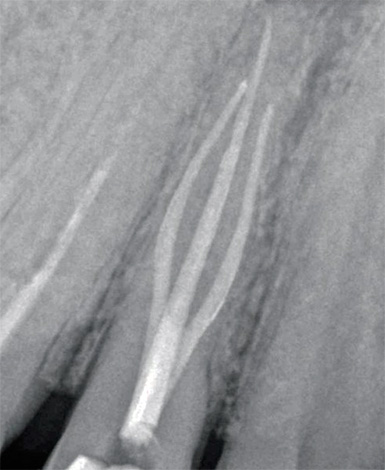

- riempire i canali mediante condensazione laterale fredda di perni di guttaperca con pasta o utilizzando il sistema Thermafil per l'otturazione;

- immagine di controllo (radiografia).

Un microscopio in endodonzia viene utilizzato, in particolare, per diagnosticare il numero di canali radicolari e la qualità del loro passaggio. Il trattamento della pulpite di un dente a tre radici al microscopio consente di trovare e trattare rapidamente anche i passaggi più difficili e ci sono molti casi simili nella pratica di un dentista.

Un microscopio endodontico ci consente di dire con quasi il 100% di certezza alla fine del trattamento che tutti i canali sono stati passati e correttamente sigillati. È lui che ti consente di controllare ogni fase del trattamento della pulite, prevenendo ulteriori complicazioni. Il trattamento tradizionale senza l'uso di un microscopio è spesso associato alla presenza di conseguenze negative a lungo termine, ad esempio a causa del fatto che il medico semplicemente non ha potuto vedere il canale aggiuntivo nel dente e lo ha perso durante il trattamento, lasciando una polpa infetta al suo interno.